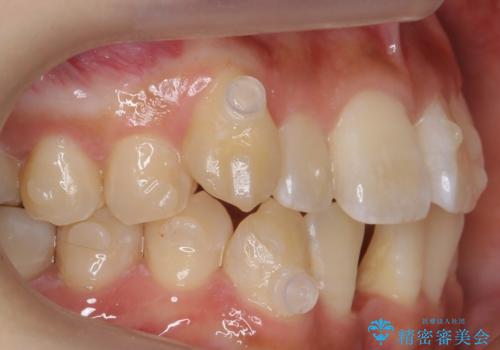

八重歯 インビザラインで抜歯矯正 ただし1本のみの抜歯で済みます

- 八重歯を治したいと来院。

古典的な治し方ですと上下左右4本抜歯してワイヤー矯正です。

今回は口元も出ていないうえに、右上のみの八重歯のため奥歯を後ろに下げて治療しました。

ただし、下の前歯は入りきらない為1本のみ抜歯しています。

右上の犬歯をおろしてくるのに、顎間ゴムを使用しています。